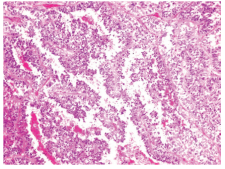

Assinale a alternativa que apresenta uma imagem capturada por microscopia de campo claro.